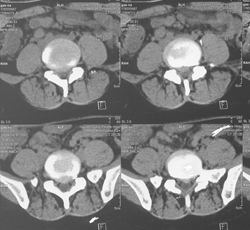

经典病例一

高* 女,腰痛伴左臀部疼痛麻木,左足麻木半月。

查体:腰5骶1棘间及左棘旁压痛、叩痛明显,疼痛向左臀部放射,左臀部外侧及左足底皮肤感觉减退,左跟腱反射减弱,左侧直腿抬高试验阳性(40°),加强试验阳性。

腰椎MRI示:L5S1椎间盘突出,左侧神经根受压。

(图)术前CT